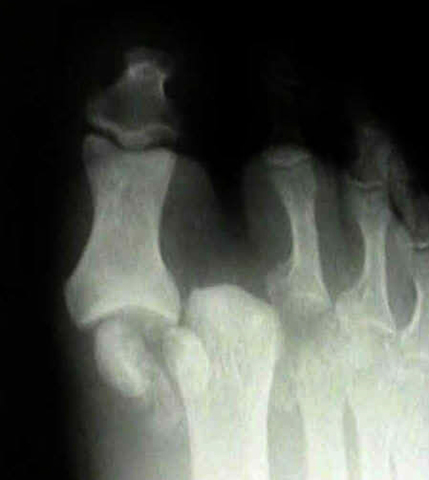

Травма диагностируется на основе визуального осмотра и рентгеновского снимка.

Диагностика Вывихов фаланг пальцев стопы:

Диагностика вывихов пальцев основывается на анамнезе, характерной деформации и положении пальцев, укорочении, ограничении функций, пружинящей неподвижности и результатах рентгенографии.

Наиболее часто встречаются вывихи дистальной фаланги I пальца, что связано с большой подвижностью этого сустава и высокой функциональной нагрузкой на I палец. Второе место занимают вывихи фаланг IV пальца. Вывихи средних пальцев встречаются реже, поскольку они лучше защищены благодаря центральному расположению. Вывихи пальцев стопы чаще происходят в тыл и в стороны, а вывихи в подошвенную сторону крайне редки из-за мощного связочно-сумочного аппарата в этой области.